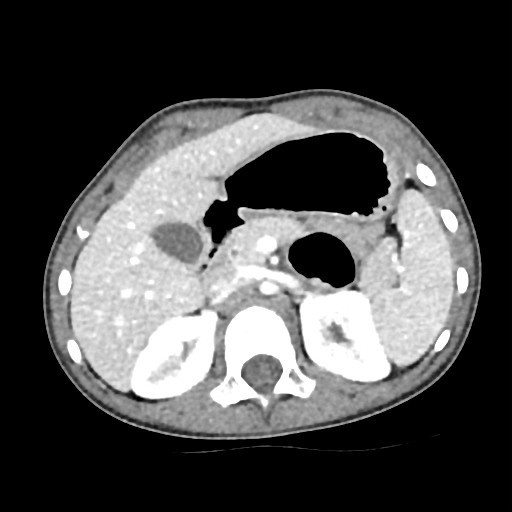

Debido a la persistencia de la distensión abdominal, se realiza una ecografía abdominal, que resulta normal y una radiografía de abdomen simple, donde se aprecia distensión de asas abdominales hasta íleon terminal, que inicialmente se asocia a posible gastroparesia posinfecciosa. Posteriormente, se amplía el estudio con un tránsito gastro-duodenal, objetivándose un “stop” al paso de contraste baritado en segunda/tercera porción duodenal-ángulo de Treitz (Figura 1). Ante la sospecha de obstrucción intestinal por una membrana duodenal, se indica una gastroduodenoscopia, que resulta normal.

| Figura 1. Tránsito digestivo superior. Se visualiza un stop a la progresión del contraste a partir del ángulo de Treitz. Dilatación del territorio proximal al stop |

Las pruebas de imagen utilizadas en estos casos, tales como la radiografía de abdomen, ecografía, tránsito digestivo superior y tomografía computarizada, normalmente objetivan datos inespecíficos compatibles con la obstrucción intestinal (dilatación de asas, niveles hidroaéreos), pero no suelen obtener una clara visualización directa de la propia brida. Por este motivo, el abordaje diagnóstico-terapéutico suele ser quirúrgico, más frecuentemente mediante laparoscopia exploradora, precisando en ocasiones una laparotomía1-4.